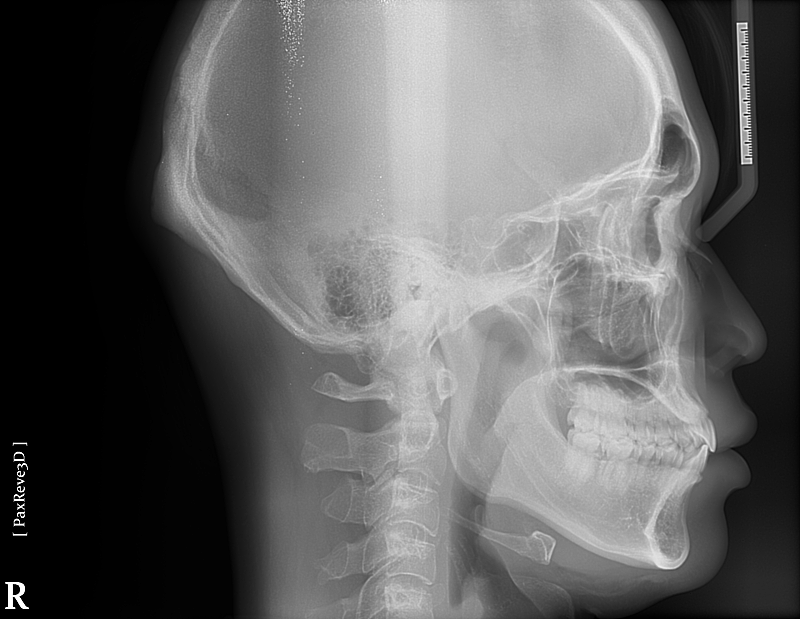

질문4. 제가 가끔 오른쪽 턱관절이 따닥소리나고 통증이 있을때가 있는데 파노라마 사진보면 관절구나 전체적인 턱 상태가 정상일까요?

• 4번 째 사진

4. 현재 상태에서는 정확한 턱관절 상황을 알 수 없으나 사진 상으로 보아서는 크게 문제가 되는 부분은 없습니다. 물론 정확한 판단을 위해서는 ct 및 방사선 뷰가 필요합니다.

-턱관절에 통증이 잇거나 소리가 난다면 턱관절에 문제가 있을수 잇습니다. 통증이 지속되거나 증가된다면 턱관절 검사를 받아보시는게 좋을것같습니다.